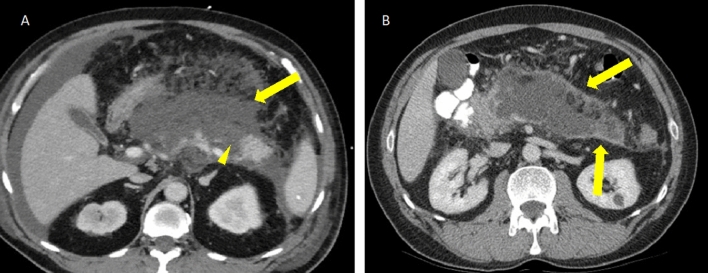

Fig. 11.

Peripancreatic and pancreatic collections in necrotizing pancreatitis. A Axial IV contrast-enhanced CT in a patient with acute NP and ANCs involving the pancreatic parenchyma (arrowhead) and the peripancreatic tissues (arrow). B Axial IV contrast-enhanced CT in a patient with NP and a large area of WON occupying the pancreatic body and tail with an enhancing capsule (arrows). Note the heterogeneous appearance of the collections in NP which contains fluid density intermixed with fat density

Fig. 12.

Necrotic debris in walled-off necrosis. A Axial IV contrast-enhanced CT in a patient with WON involving the pancreatic body and tail with subtle heterogeneous density in the collection indicating necrotic debris (arrowhead). B Axial T2W sequence in the same patient obtained the next day showing comparatively more obvious necrotic debris in the same WON as indicated by heterogeneous signal intensity (arrowhead)